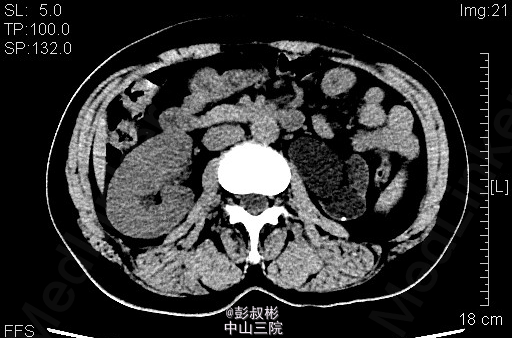

患者女性,47岁,左腹部胀痛1月余。既往有“双肾结石”病史10余年。其余见双肾CTU。根据检查判断肾的病变?